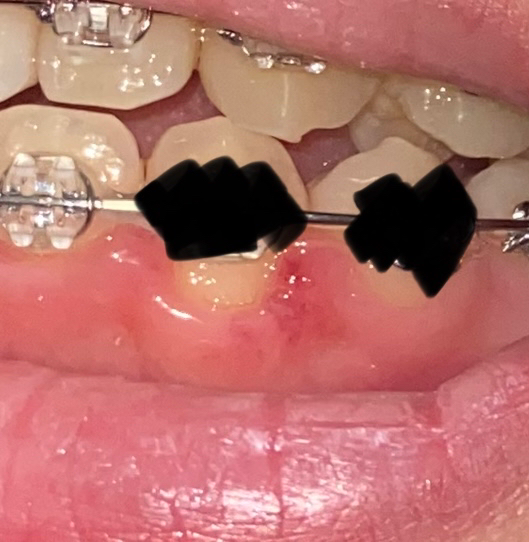

잇몸에 상처가 났는데 이빨이 더 드러났어요 이래도 괜찮은건가요?

칫솔을 좀 억센걸 썼더니 상처가 난 것 같더라구요.. 근데 같은 이거랑 같은 위치에 있는 이빨이랑 비교해봤는데 잇몸이 아래로 좀 내려가서 이빨 아랫부분이 더 보이더라구요.. 이래도 괜찮은건가요? 병원 가야할까요?

• 1번 째 사진

말씀하신 치아는 견치라고 해서 우리 몸에서 가장 긴 뿌리를 가지고 있는 치아입니다. 다른 치아에 비해 잇몸이 상대적으로 내려가 보이는 것이 정상적입니다. 또한 잇몸에 난 상처도 크게 걱정할 정도는 아니며 2주 이내에 회복될 것으로 보입니다.

치아 사이 잇몸에 염증이 생기신거 같습니다. 일단은 치과에 가셔서 검진후 잇몸치료를 한번 받으시는게 좋을것같습니다.